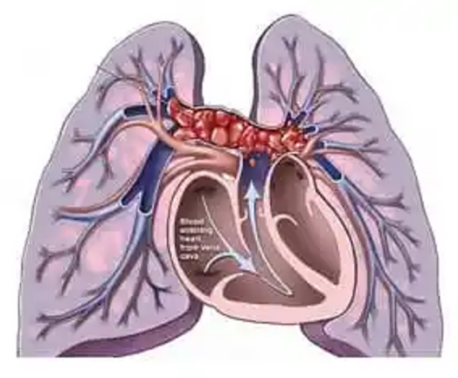

出院后虽然遵从医嘱按时吃药,但胸闷气促依旧时刻充斥着熊大爷的生活。这是因为转为慢性肺栓塞后,仅通过奥西呱和华法林等药物以很难逆转已有的肺动脉栓子,且对于限制栓子再次形成的能力也十分有限。慢性肺栓塞是以慢性呼吸困难和右心功能不全为主要表现的,严重者甚至出现低氧血症、紫绀、下肢静脉病变等表现。慢性血栓栓塞性肺动脉高压(CTEPH)是静脉血栓栓塞性疾病的并发症。与其他引起肺动脉高压的原因不同,CTEPH 有可能通过手术(血栓内膜切除术)或球囊肺血管成形术治愈。

影像学在 CTEPH 诊断中起着核心作用。肺闪烁扫描、计算机断层扫描和磁共振血管造影等技术的结合提供了非侵入性的解剖和功能信息。常规肺血管造影 (CPA) 和右心导管 (RHC) 被认为是诊断 CTEPH 的金标准方法。目前外科的肺动脉血栓内膜剥脱术是治疗慢性肺栓塞的首选方法,疗效明显,但由于其手术难度高风险大,多数综合医院的心脏外科并未广泛开展该项手术。而内科的球囊扩张术也能从一定程度改善患者长期慢性低氧的症状,是目前云南地区慢性肺动脉栓塞患者在药物治疗不理想后首选的干预方案。